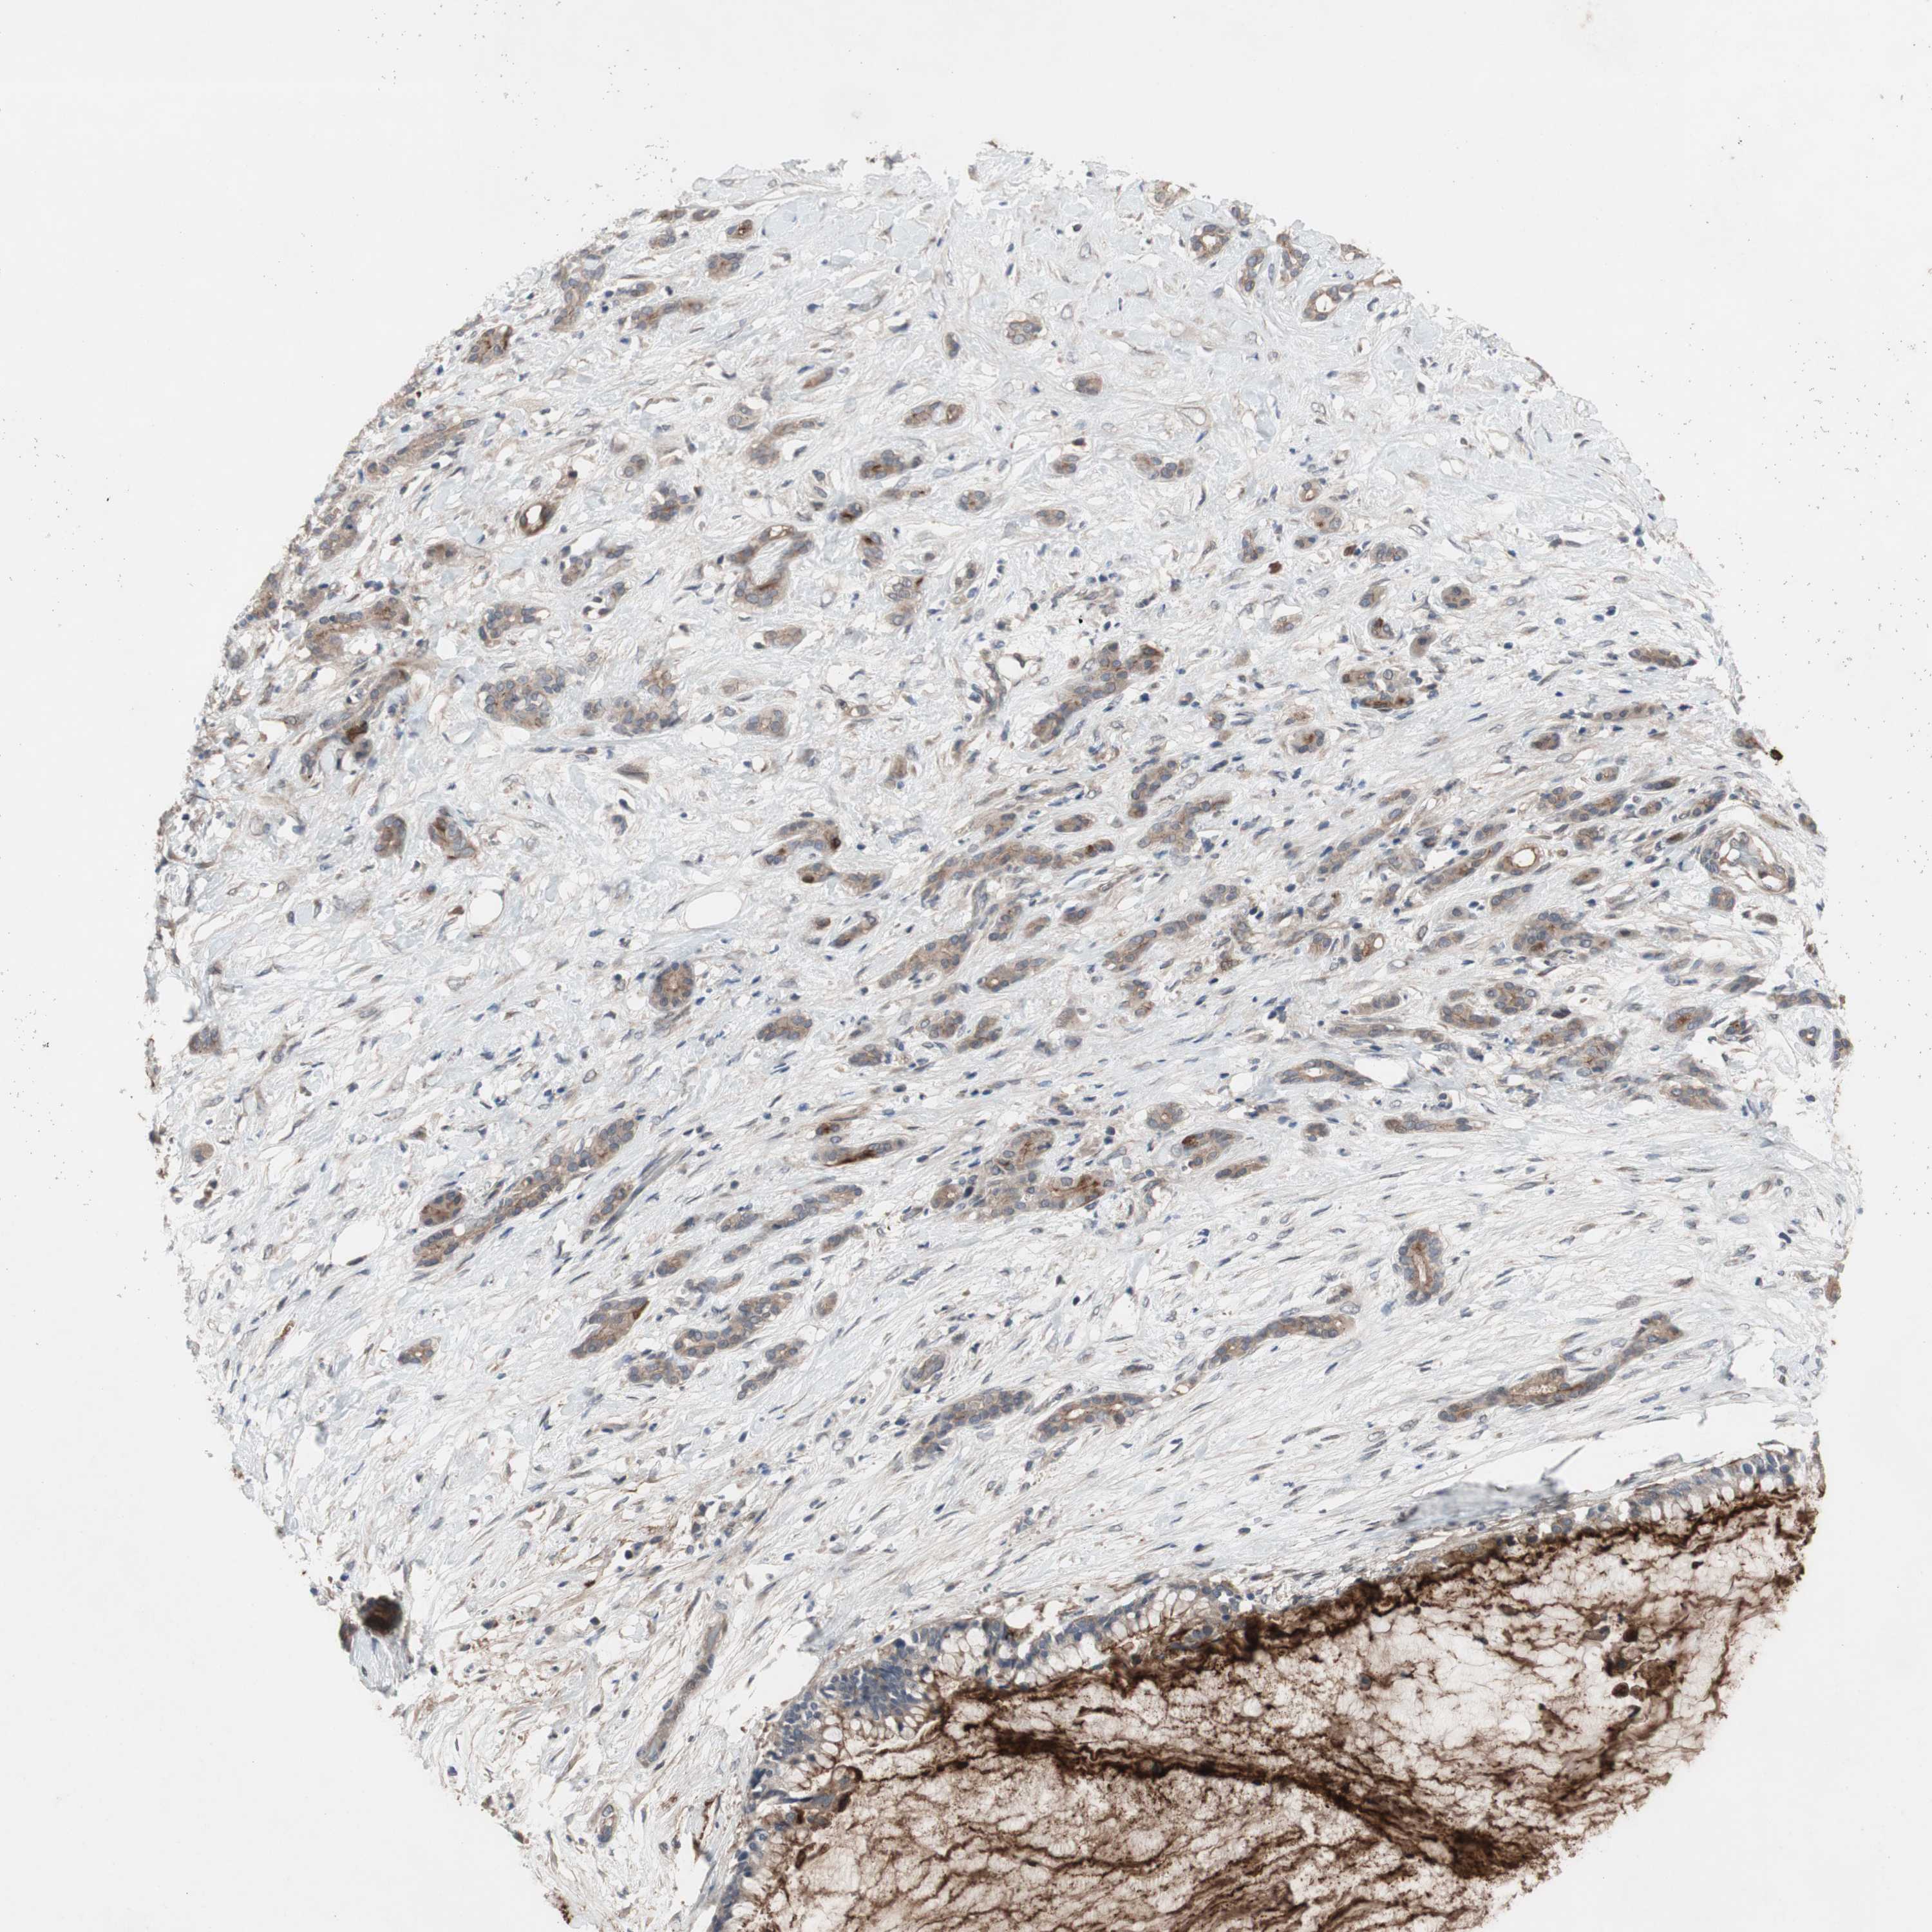

PANCREATIC CANCER - Protein expressioni

A mouse-over function shows sample information and annotation data. Click on an image to view it in a full screen mode. Samples can be filtered based on level of antibody staining by selecting one or several of the following categories: high, medium, low and not detected. The assay and annotation is described here.

Note that samples used for immunohistochemistry by the Human Protein Atlas do not correspond to samples in the TCGA dataset.

Antibody stainingi

Antibody staining in the annotated cell types in the current human tissue is reported as not detected, low, medium, or high, based on conventional immunohistochemistry profiling in selected tissues. This score is based on the combination of the staining intensity and fraction of stained cells.

Each image is clickable and will lead to virtual microscopy that enables deeper exploration of all samples and also displays staining intensity scores, fraction scores and subcellular localization as well as patient and tissue information for each sample.

Antibody HPA009291

Staining

High

Medium

Low

Not detected

Intensity

Strong

Moderate

Weak

Negative

Quantity

>75%

75%-25%

<25%

None

Location

Nuclear

Cytoplasmic/membranous

Cytoplasmic/membranous,nuclear

Adenocarcinoma, NOS